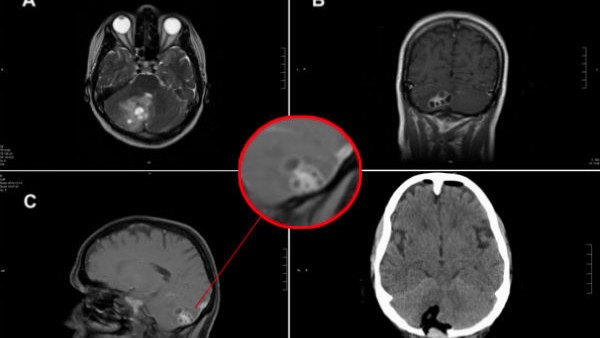

Rosemary Alverez was only 37 when she received the devastating news that doctors had found a tricky and dangerous tumour in her brain.

Her condition quickly began to deteriorate and she lost the ability to swallow and balance as her extremities went numb. She was rushed into hospital for an operation.

It was during this operation that the doctor found something that would make a brave man whimper. Instead of finding a dangerous tumour in Rosemary's brain, he found a friendly tapeworm that had nestled into her cranium. Props have to go to the brave surgeon for not passing out on the spot and managing to remove the interloper.